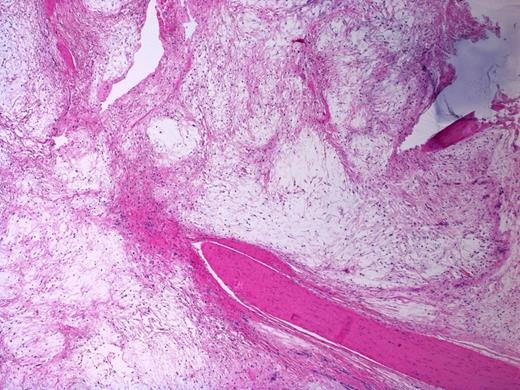

Involvement of a tendon (lower right corner) by the myxoma. Note bluish dense extracellular mucin in the right upper corner. H&E stain, 40X magnification

Sections of the lesion showed dense fibrous tissue with nodules of extracellular myxoid material containing scattered histiocytes and stellate to spindled fibroblastic cells. There was no evidence of necrosis, atypia or malignancy; this was consistent with Juxta-articular myxoma. (Figure 4 and 5). At one year follow-up there has been no sign of recurrence.